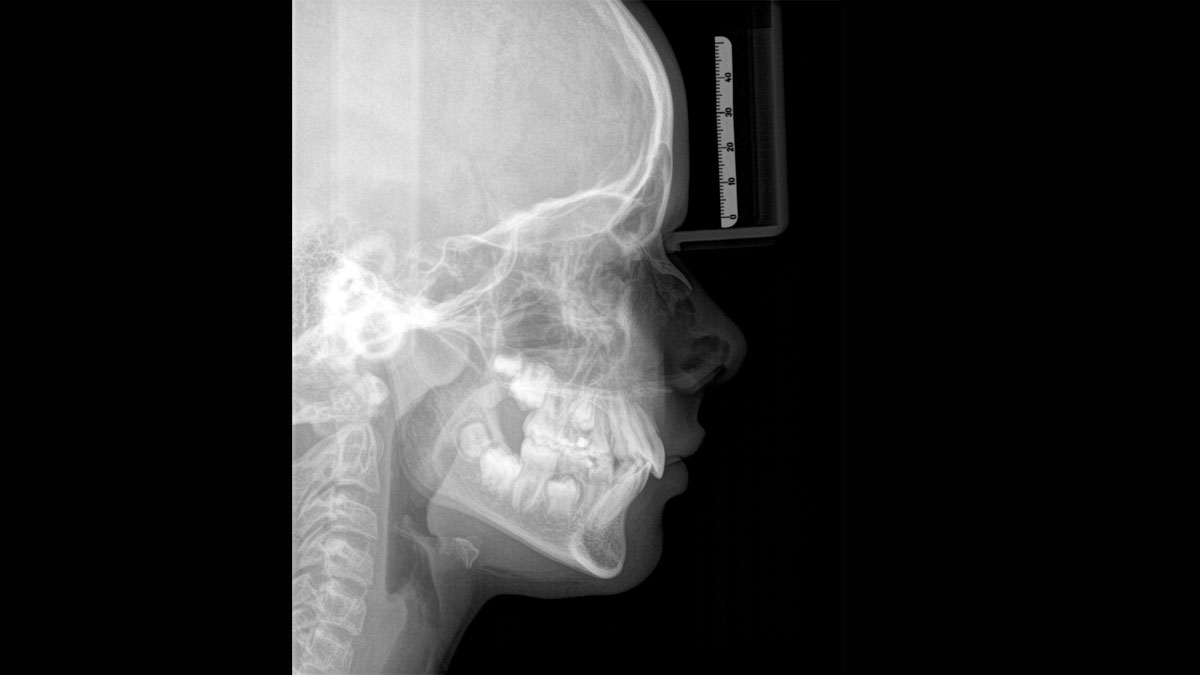

Para obtener imágenes panorámicas excepcionales con alta nitidez. Puede elegir un brazo cefalométrico derecho o izquierdo opcional, que puede reacondicionarse en cualquier momento